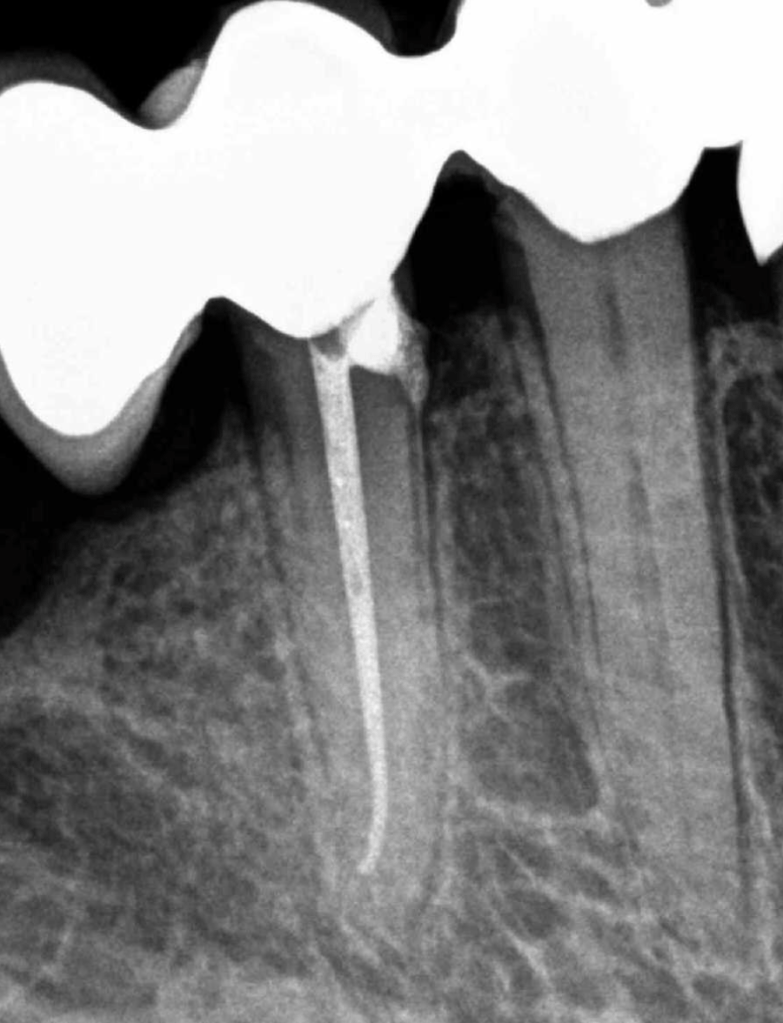

Incisivo superior Endo-perio

Incisivo superior trauma